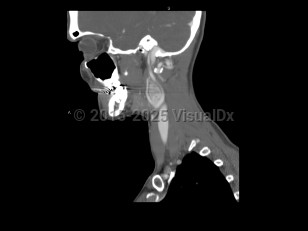

Sore throat, Neck mass, 50-59 year old Female

Peritonsillar abscessPeritonsillar abscess